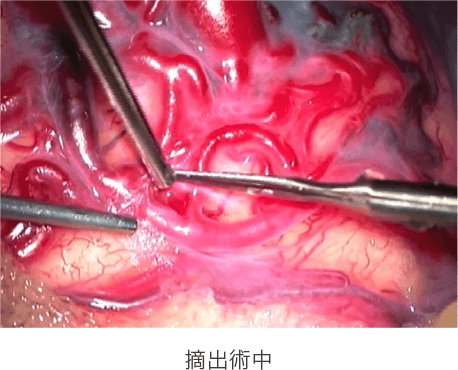

その名の通り、開頭してAVMを摘出する方法です。摘出した直後から、出血や再出血の危険性はなくなるため、もっとも短期間で根治が得られる治療法です。顕微鏡を用いながら、周囲の正常な脳組織から剥離して摘出しますが、AVM自体が血管の固まりであるため、摘出に際して非常に繊細な手技を要します。重要な機能を有する脳に存在する病変や巨大な病変などに対しては、本治療法を選択することが困難な場合もあります。